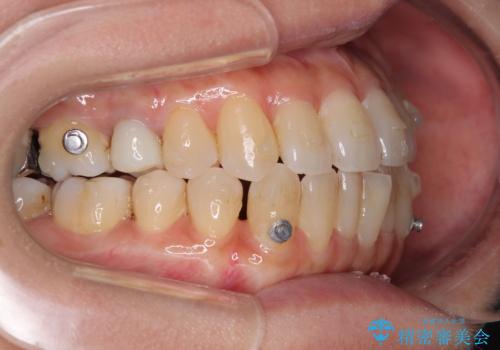

- 矯正装置

- インビザライン

- 前歯のデコボコや八重歯を治したいとのことで来院された患者様です。

受け口傾向の骨格であり、前歯はクロスバイトまたは切端咬合となっており、下顎を中心に歯列全体の後方移動を行い、IPR(歯と歯の間を削る)によってデコボコが解消するように設計し、インビザラインにより治療を行うこととしました。